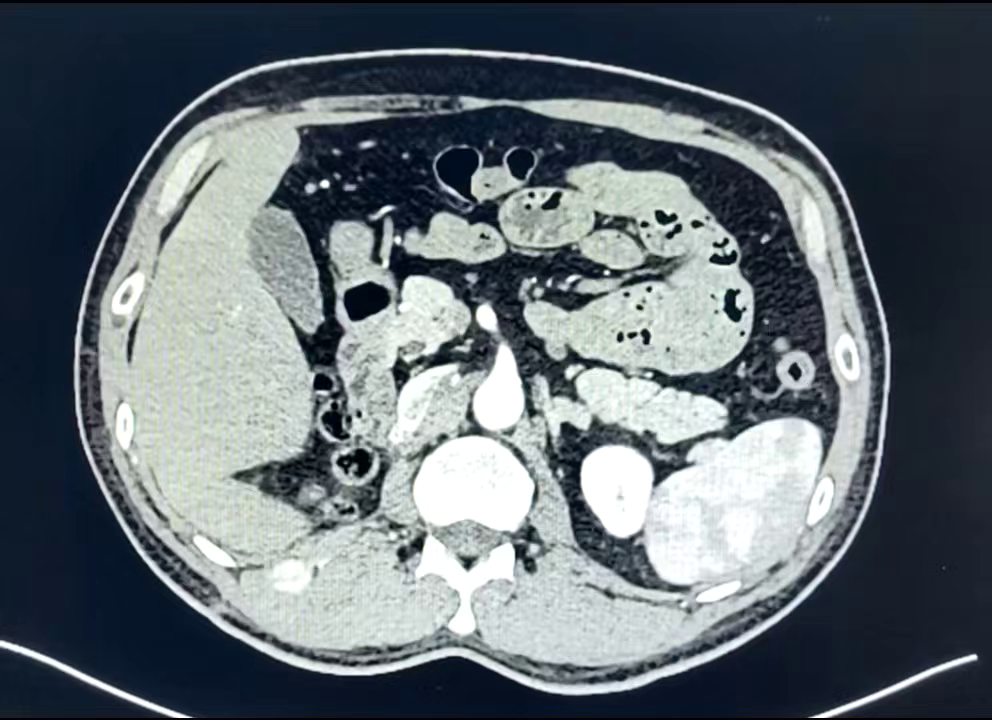

现病史:2024-08,患者因“右侧腰部阵发性胀痛痛1+月,肉眼血尿伴血凝块1+周”就诊于金堂县仁爱医院就诊,彩超提示:"右肾弱回声团块8.6*6.8cm(未见报告)",患者为进一步诊疗至广元市中心医院,肾及肾上腺 CT 提示:"右肾占位,肾静脉癌栓形成,肝门区及右侧膈脚旁淋巴结转移",建议手术治疗。患者为求手术治疗至我院,门诊以"右肾肿瘤"收泌尿外科住院治疗。

2023-08-31泌尿系统超声造影:造影前右肾中上份探及大小约8.5cm×5.9cm实性团块,边界部分欠清,形态较规则,内部回声不均匀,其内可见强回声,内可见较丰富血流信号。注入造影剂后右肾中上份实性团块早于正常肾实质增强,达峰时呈不均匀行高增强,内可见不规则无增强区,团块内造影剂消退较慢,周边可见不连续增强环。

右肾中上份实性团块超声造影为富血供肿瘤性病变,考虑肾细胞癌。

2023-09-01全腹增强MRI: 右肾见一类椭圆形肿块,大小约80mm×65mm×74mm,呈等稍长T1、等长T2信号、弥散受限,增强扫描明显强化、强化不均匀,右肾盂受压变形,病灶累及肾周间隙及肾后筋膜,肾后筋膜增厚毛糙呈结节样,部分肾静脉稍显不清,肾血管旁见数个小淋巴结显示,大者短径约4mm;以上考虑右肾肿瘤占位,透明细胞癌?预计分期T3aNOMx。

免疫组化: PAX8(+), CAIX (+),CD10(+), CK (+),CD117(少许+),CK20(-),CK7(-), CgA (-),HMB45(-),S100(-),TFE3(-), syn (-/+),Ki67(约30%)。结合组织形态及免疫组化结果,符合肾细胞癌。

透明细胞肾细胞癌( WHO :3-4级)。

2023-09全麻全麻下行腹腔镜下右肾根治性切除术、肾周粘连松解术。

术后病理:透明细胞肾细胞癌( WHO / ISUP :3级)。

2023-09培唑帕尼治疗至今;

2024-04腹部增强CT;

疗效评估:SD。